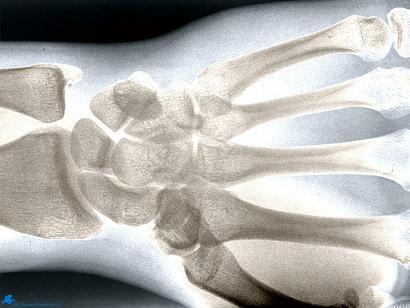

La radiographie pratiquée aujourd'hui, permet, grâce aux rayons X, d'observer les organes internes du corps et de dépister inflammations et maladies diverses.

La radiographie utilise les rayons X, ceux –ci ont les mêmes propriétés que les rayons lumineux tels qu’on les connait, c'est à dire qu'ils permettent d'imprégner une plaque photographique, mais ont en plus la faculté de traverser le corps. Plus la densité du corps sera importante, moins le rayon pourra passer au travers de celui ci.

C'est grâce à ce phénomène que l'image obtenue apparaîtra plus ou moins noire. En effet, lors de la radiographie du corps humain, les rayons vont rencontrer soit des tissus, soit des muscles ou des os. Les rayons vont aisément passer à travers les tissus et la plaque qui sera impressionnée prendra une apparence sombre. A l’inverse, lorsqu’ils rencontreront des os, ceux-ci seront totalement arrêtés. Il n’y aura donc aucune impression sur la plaque, et celle-ci restera blanche.